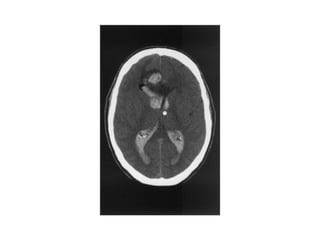

CT SCAN OF BRAIN

Ct scan lecture